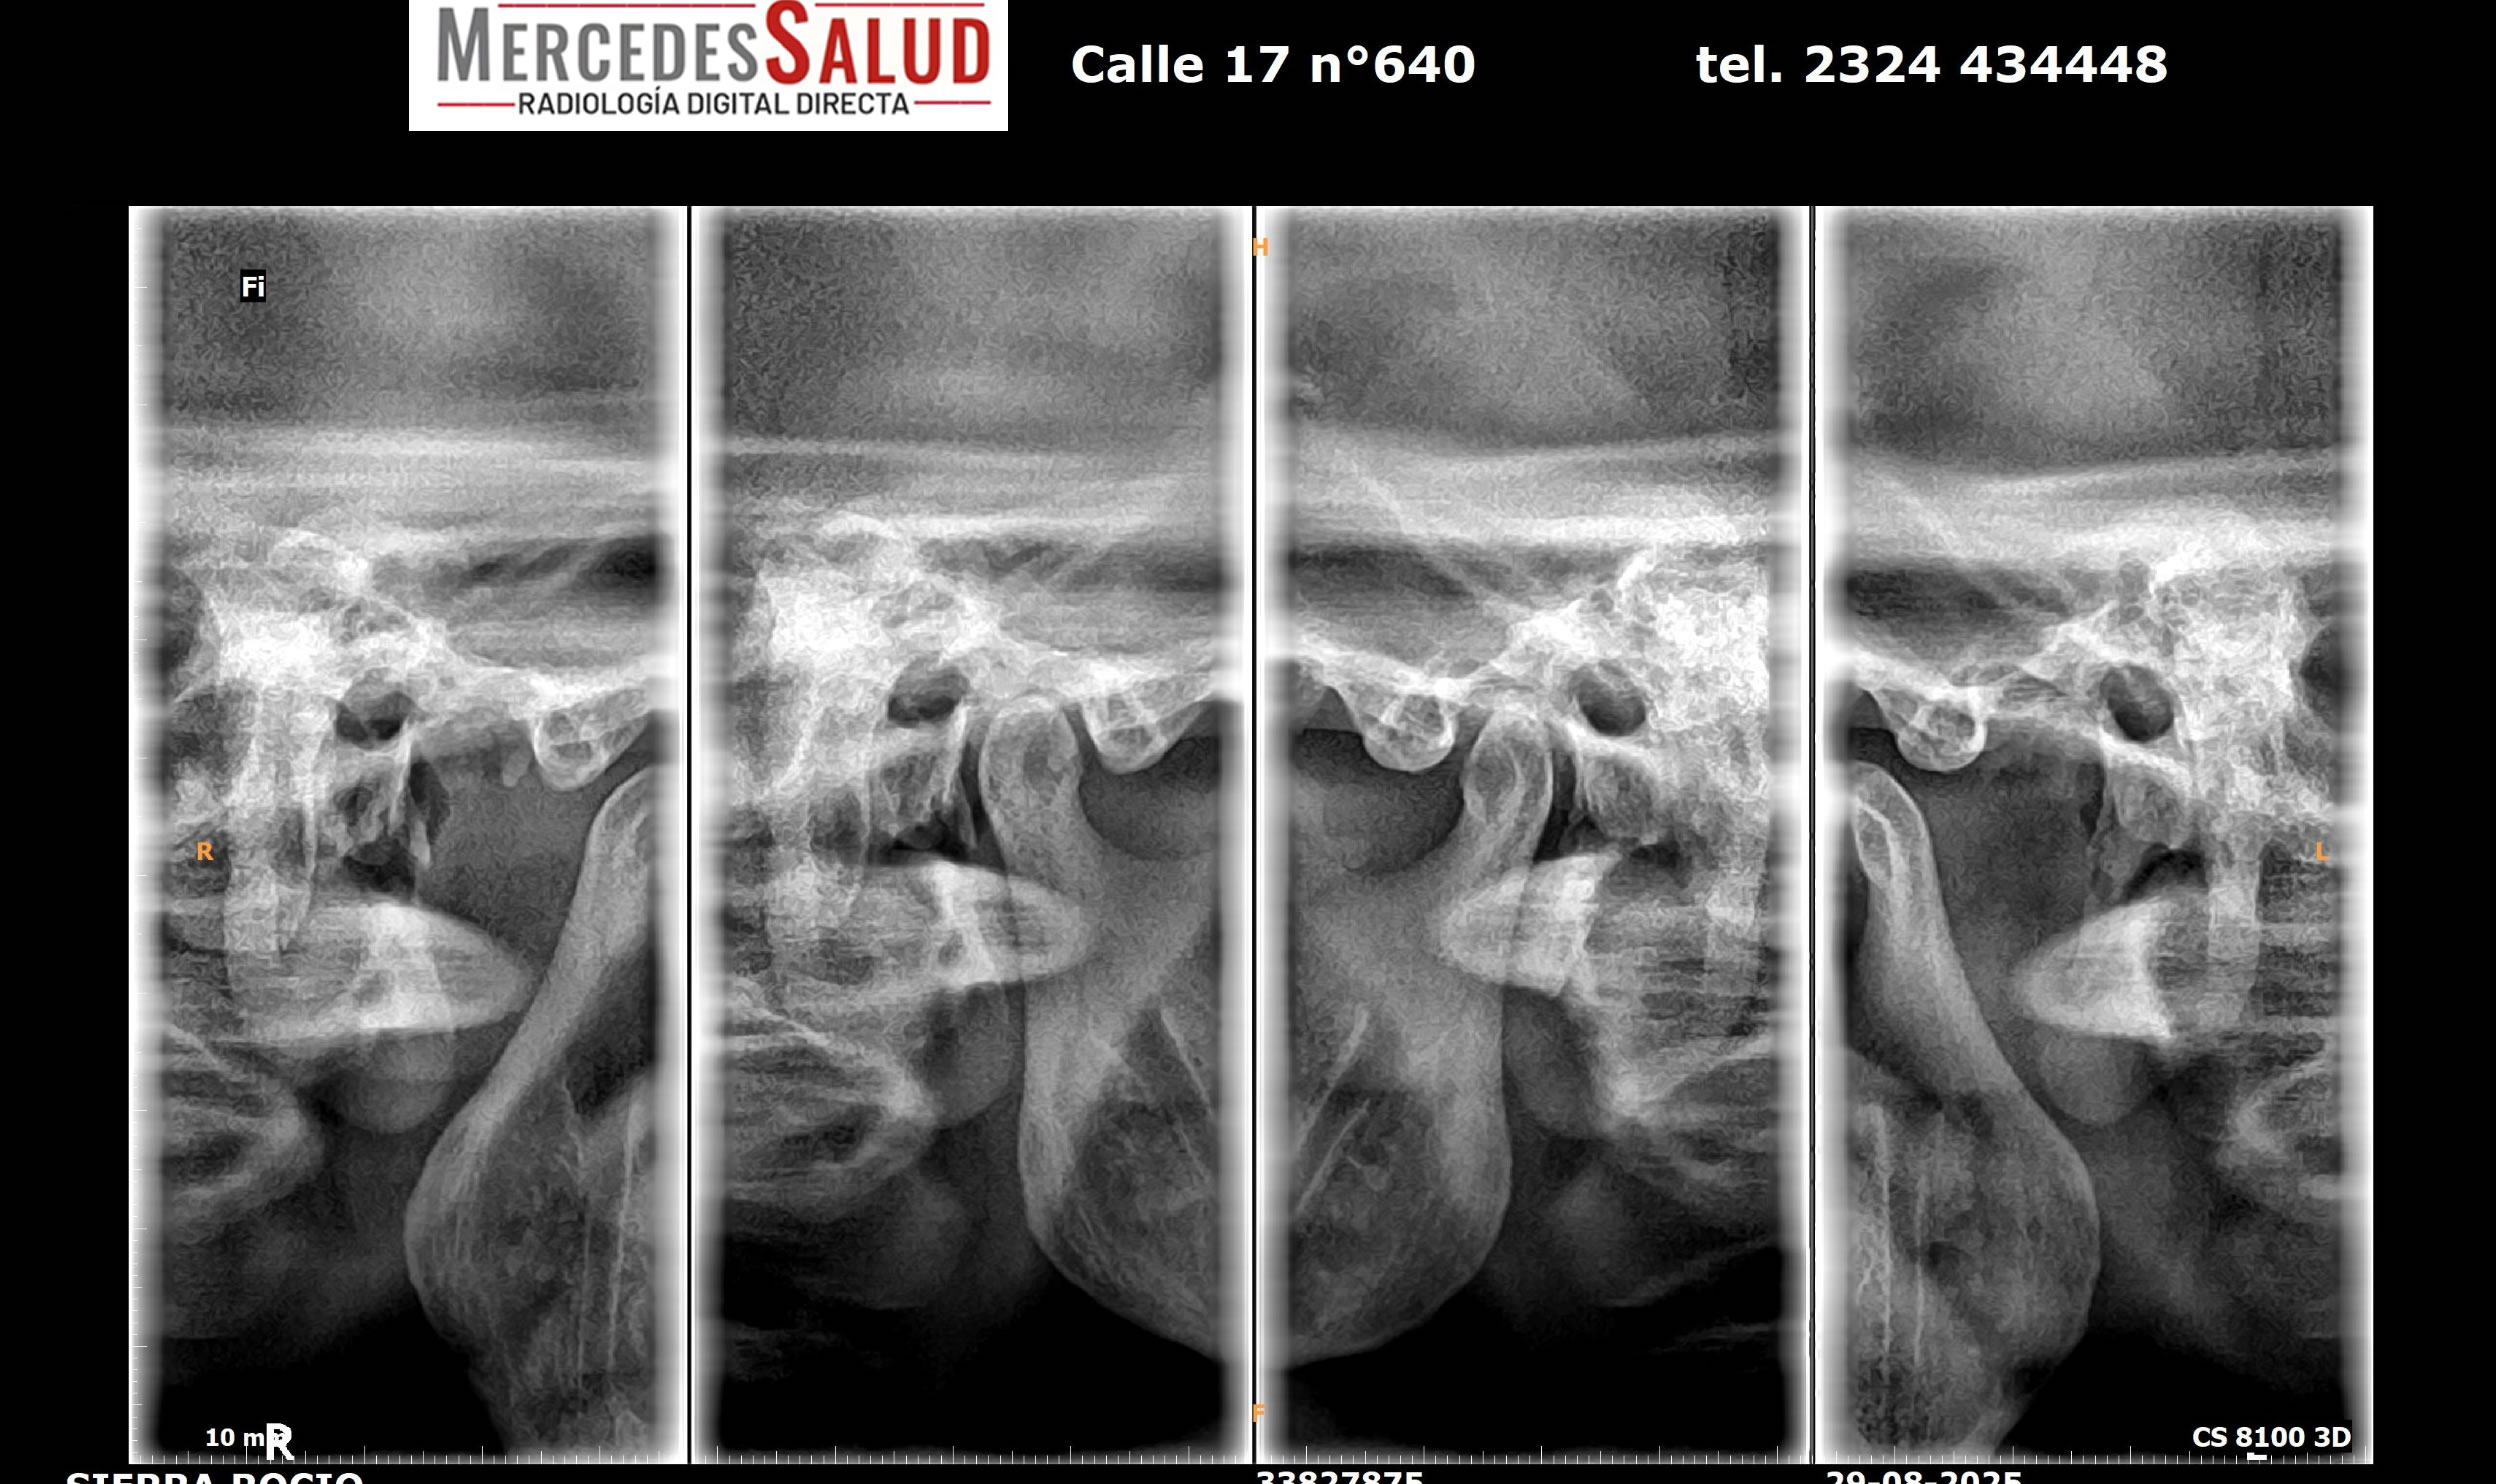

Tomografía Dental 3D: «Elite» del diagnóstico

La gran innovación para Mercedes es la incorporación de un equipo Carestream CS8100 3D, un tomógrafo de Maxilar que es el único de su tipo en la ciudad y la región. Este aparato es crucial para la odontología de alta complejidad y la cirugía maxilofacial, siendo altamente demandado por profesionales que realizan implantes y procedimientos quirúrgicos.

«Estamos ofreciendo el servicio de imágenes de radiología digital directa con un equipo Pimax y, algo innovador para Mercedes, el equipo que hace tomografía de Maxilar,» explicó el Lic. Quiroga. «Es el único que hay en Mercedes, y hoy en día estamos trabajando muy bien con los odontólogos que hacen macis facial e implantes.»

Además del tomógrafo dental, que realiza panorámicas dentales y tomografías, y permite realizar laminografías de la articulación temporomandibular (ATM) y placas de macizo facial para casos como fracturas, el servicio también ofrece estudios especializados como espinogramas y mediciones de miembro inferior con el equipo Pimax. Estos estudios de alta calidad son muy requeridos por traumatólogos de la ciudad y zonas aledañas. La calidad de imagen es tal que, según el Lic. Quiroga, pacientes de ciudades vecinas viajan a Mercedes para ser atendidos.